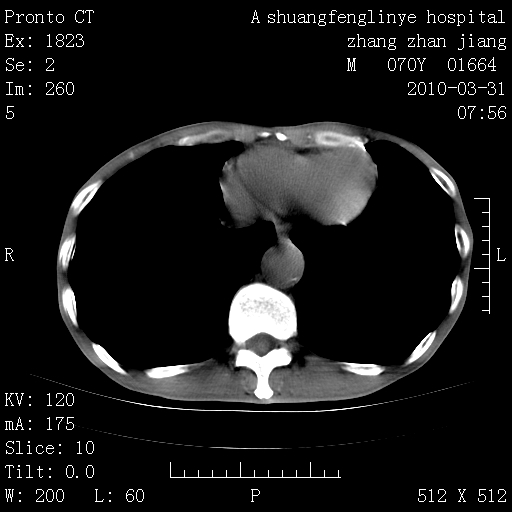

双上肺继发型tb并左上空洞形成,主动脉冠脉钙化。

1)两肺上叶继发性肺结核并左肺上叶空洞形成。2)冠状动脉及主动脉钙化。